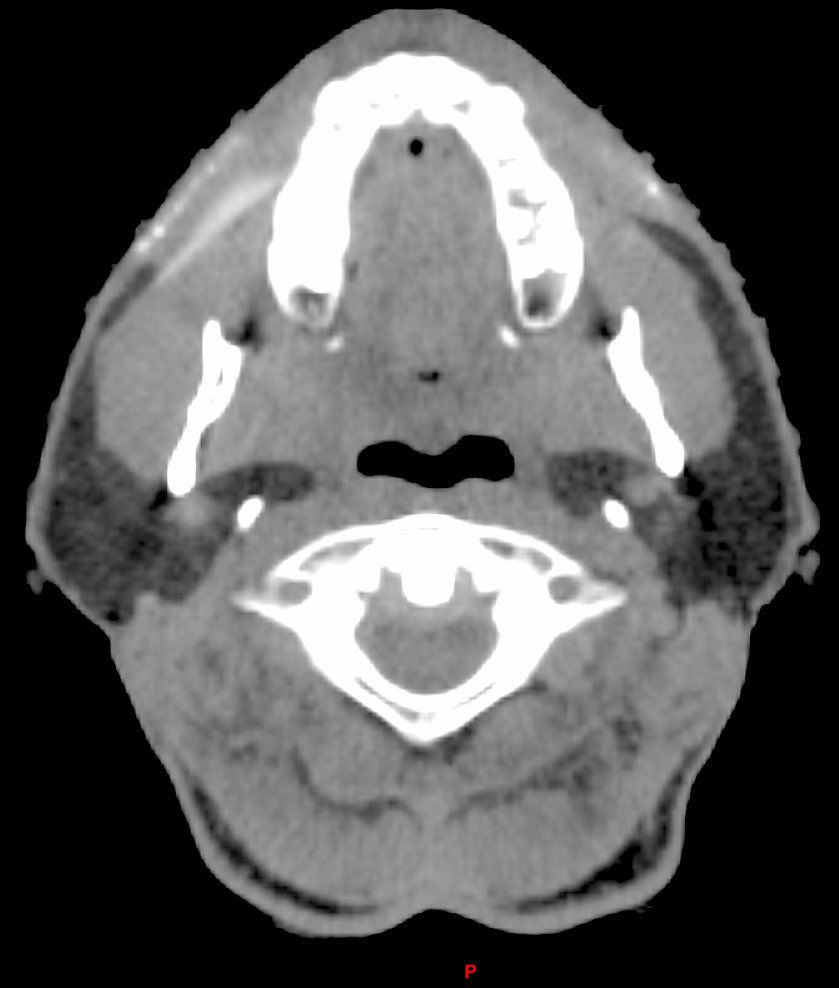

The diagnostic evaluation consists mainly of ultrasound scan, CT, and/or MRI showing multiple thin walled cysts.4 (See CT scans above.)